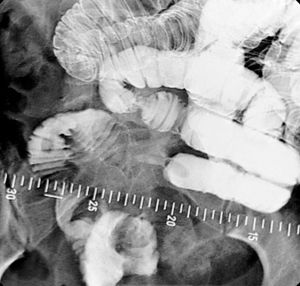

소장 조영술은 소장의 전체적인 형태와 병변을 확인하는 검사다. 바륨 추적 검사는 소장을 연구하는 데 사용된다.[1]바륨은 경구 투여하며, 때로는 디아트리조산(Gastrografin)과 혼합하여 장 통과 시간을 줄인다. 정맥 내 메토클로프라미드를 혼합물에 첨가하여 위 배출을 촉진하기도 한다.[20] 바륨 식사 후 600ml의 0.5% 메틸셀룰로스를 경구 투여하여 바륨이 소장을 통과하는 데 걸리는 시간을 줄이고, 조영제로 채워진 소장의 투명도를 높여 소장 추적 검사 영상을 개선할 수 있다.[17] 장 통과 시간을 줄이는 다른 방법으로는 바륨 식염수 혼합물 투여 후 얼음처럼 차가운 생리 식염수를 추가하거나[18] 건조한 식사를 제공하는 것이다.[19]

이후 20~30분 간격으로 앙와위 자세에서 X선 촬영을 한다. 실시간 투시경 검사를 사용하여 장 운동성을 평가한다. 영상 촬영 중에는 방사선 전문의가 장 루프를 분리하기 위해 복부를 누르거나 촉진할 수 있다. 검사에 필요한 총 시간은 장 운동성 또는 통과 시간에 따라 다르며 1~3시간 사이로 변동될 수 있다.[20]

소장 추적 검사의 경우, 바륨을 경구 투여하며, 때로는 디아트리조산(Gastrografin)과 혼합하여 장 통과 시간을 줄인다. 정맥 내 메토클로프라미드를 혼합물에 첨가하여 위 배출을 촉진하기도 한다.[20] 20~30분 간격으로 앙와위 자세에서 X선 촬영을 하며, 실시간 투시경 검사를 사용하여 장 운동성을 평가한다. 검사에 필요한 총 시간은 장 운동성 또는 통과 시간에 따라 다르며 1~3시간 사이로 변동될 수 있다.[20]

- 소장 질환: 장액주입술은 소장 질환 진단에 매우 정확하며, 다른 영상 기법으로 보이지 않는 병변을 감지할 수 있다.[5] 특히 소장 점막 이상 진단에 있어 캡슐 내시경 및 이중 풍선 내시경보다 우수한 결과를 보인다.[24]